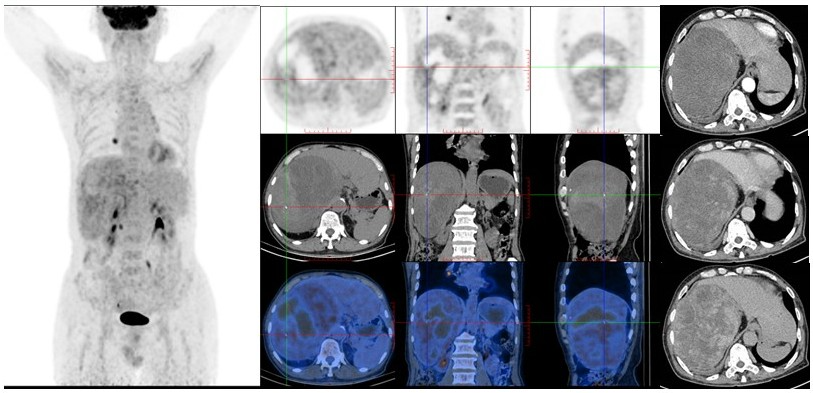

病例(2为一老年男性,因发热伴间断性后背部坠胀、疼痛不适就诊;增强CT腹膜后巨大占位,平扫呈混杂稍低密度,其内部及边缘见点状钙化少许脂肪密度,增强扫描呈不均匀强化;18F-FDG PET/CT示占位代谢轻度不均匀增高;(右侧腹膜后肿物)穿刺病理为脂肪肉瘤

病例2. 男,81岁,发热伴间断性后背部坠胀、疼痛不适脂肪肉瘤